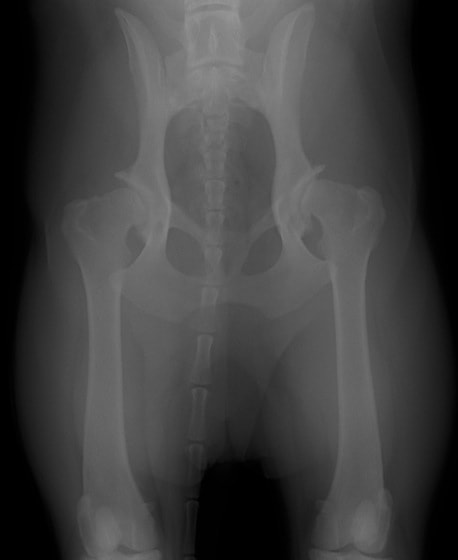

Orthopedic Foundation for Animals (OFA) が推奨するX線撮影法にて股関節の緩み、整合性、骨関節炎病変の程度を評価します。

PennHIP法(ストレスX線撮影法)

股関節の緩みを客観的に評価することが可能です。University of Pennsylvania Improvement Program (PennHIP) に評価を依頼する方法です。この機関に依頼する場合、Penn HIP により認定されている獣医師により撮影された特別な撮影像が必要となります。当院では、PennHIP 認定獣医師の資格がありますので撮影が可能です。4ヵ月齢から評価可能ですので、股関節形成不全の発症の有無を知りたい場合にも利用可能です。(PennHIP法の詳しい説明はコチラ)

PennHIP法を実施した症例のレントゲン写真